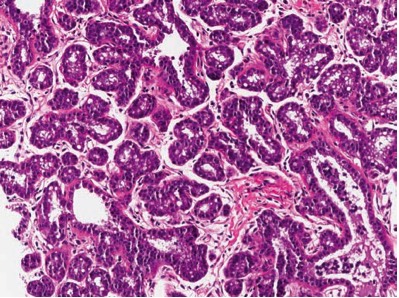

1074. У пациентки 36 лет, с пальпируемым уплотнением в молочной железе и представленным на микрофотографии биоптатом образования, нужно уточнить при сборе анамнеза информацию о